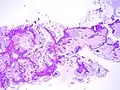

Adénocarcinome pulmonaire in situ mucineux